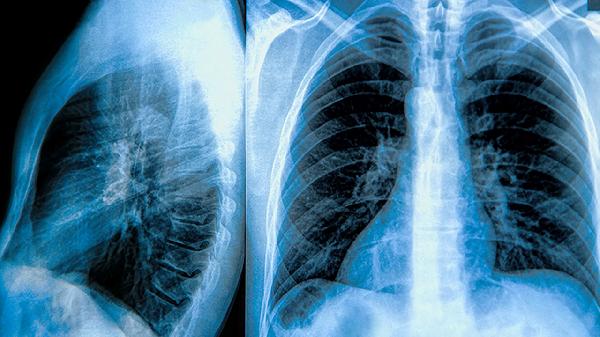

肺大泡患者需注意避免剧烈运动、预防呼吸道感染、戒烟、定期复查肺功能、保持健康体重。肺大泡是肺泡异常扩张形成的囊泡样病变,可能影响呼吸功能。

每6-12个月需进行肺通气功能检测和胸部CT复查,评估肺大泡大小变化及剩余肺功能。动态监测有助于早期发现气胸或新发病灶,医生可根据结果调整氧疗等干预方案。